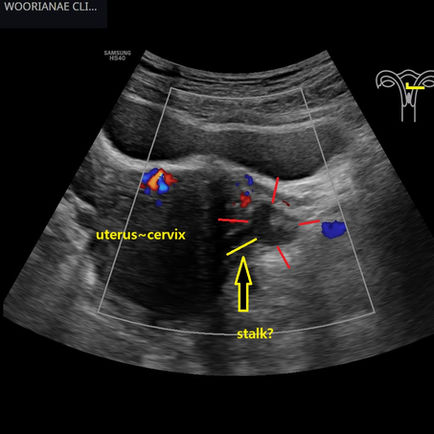

자궁옆 낭종? 종괴?? 리뷰시 줄기가 보여 장막하 근종 가능성; 복부 평가시 발견되는 골반 병변들 - 동대문구 답십리, 중곡동, 우리안애 우리안愛 내과